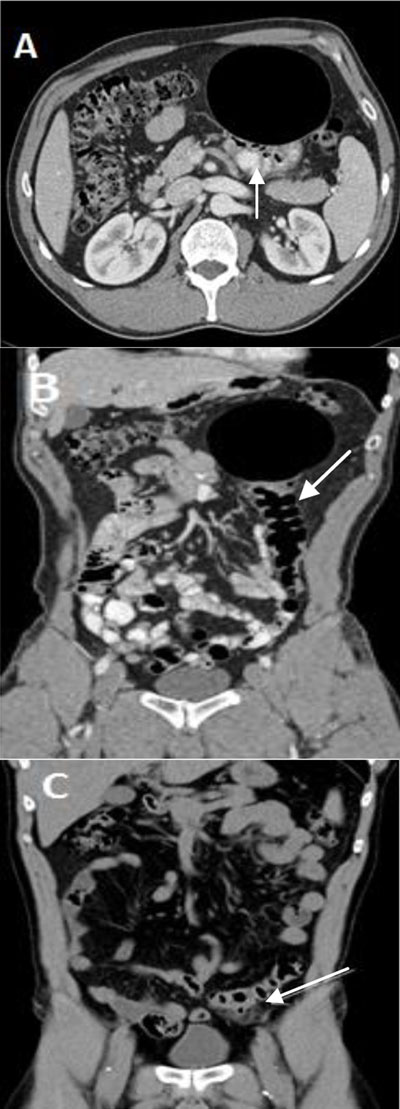

A 48-year-old male patient was referred by his general practitioner to the radiology department for evaluation of a mobile non tender abdominal mass. The patient did not report abdominal pain, nor any changes in bowel habits. His medical history included uncomplicated sigmoid diverticulitis, prostatitis and left nephrolithiasis. Previous surgeries included left kidney stone extraction. On clinical examination the abdomen was distended, soft and without tenderness, but a large tympanic mass was palpable in the left hypochondrium. Contrast-enhanced computed tomography (CT) showed a 10.4 × 8.1 cm gas-filled mass in the left hypochondrium and adjacent to the sigmoid (Figure 1A and B). The mass appear to occur at the level of a peri-diverticulitis area where no cystic mass was shown one year earlier on a CT scan (Figure 1C). The actual cystic lesion had generated the migration of the sigmoid from the left iliac fossa to the left hypochondrium (lifting balloon sign). Gastrografin enema was performed two weeks later to exclude fistulization. The exam in standing position showed focal diverticulosis adjacent to a well-defined large gas-filled cavity of 9.7 cm (Balloon sign) in the left hypochondrium (Figure 2). The lesion did not have air-fluid level or extravasation of contrast agent and it confirmed the diagnosis of a giant sigmoid diverticulum.

Figure 1

(A) and (B) Contrast-enhanced CT scan showing a 10.4 × 8.1 cm smooth-walled well-defined cystic air-filled lesion adjacent to the sigmoid (arrow) lifted in the left hypochondrium. (C) Unenhanced CT scan of the abdomen from one year earlier showed sigmoid diverticulitis (arrow) located in the left iliac fossa and without the cystic mass.